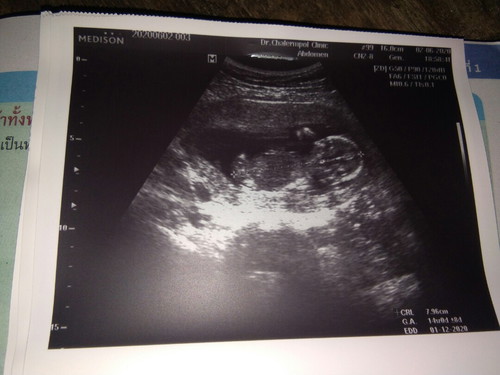

เสี่ยงครรภ์เป็นพิษ

ไปหาหมอที่ไรมีแต่เรื่องให้คนเป็นแม่ได้ลุ้น 14wเสี่ยงครรภ์เป็นพิษ 10wมีเลือดออกเสี่ยงแท้งคุกคาม สู้ๆไปด้วยกันนะคนเก่ง

ตั้งครรภ์